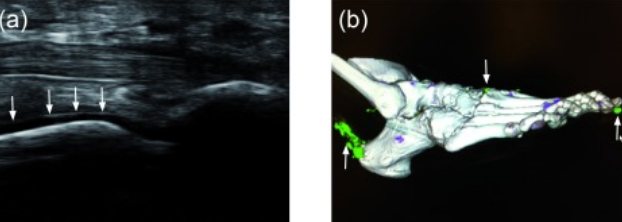

Échographie sur place

Complément indispensable, notre échographie musculo-squelettique permet d’évaluer en temps réel les tendons, ligaments et articulations, guidant les infiltrations et injections de PRP avec une précision millimétrique.